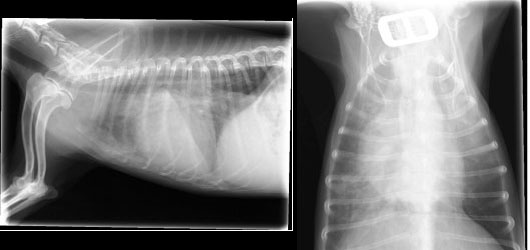

肺の状態を確認するため、胸部レントゲン検査を実施すると、心臓の拡大と肺の不透過性亢進像(白くなること)が確認されました。(図1参照)

図1